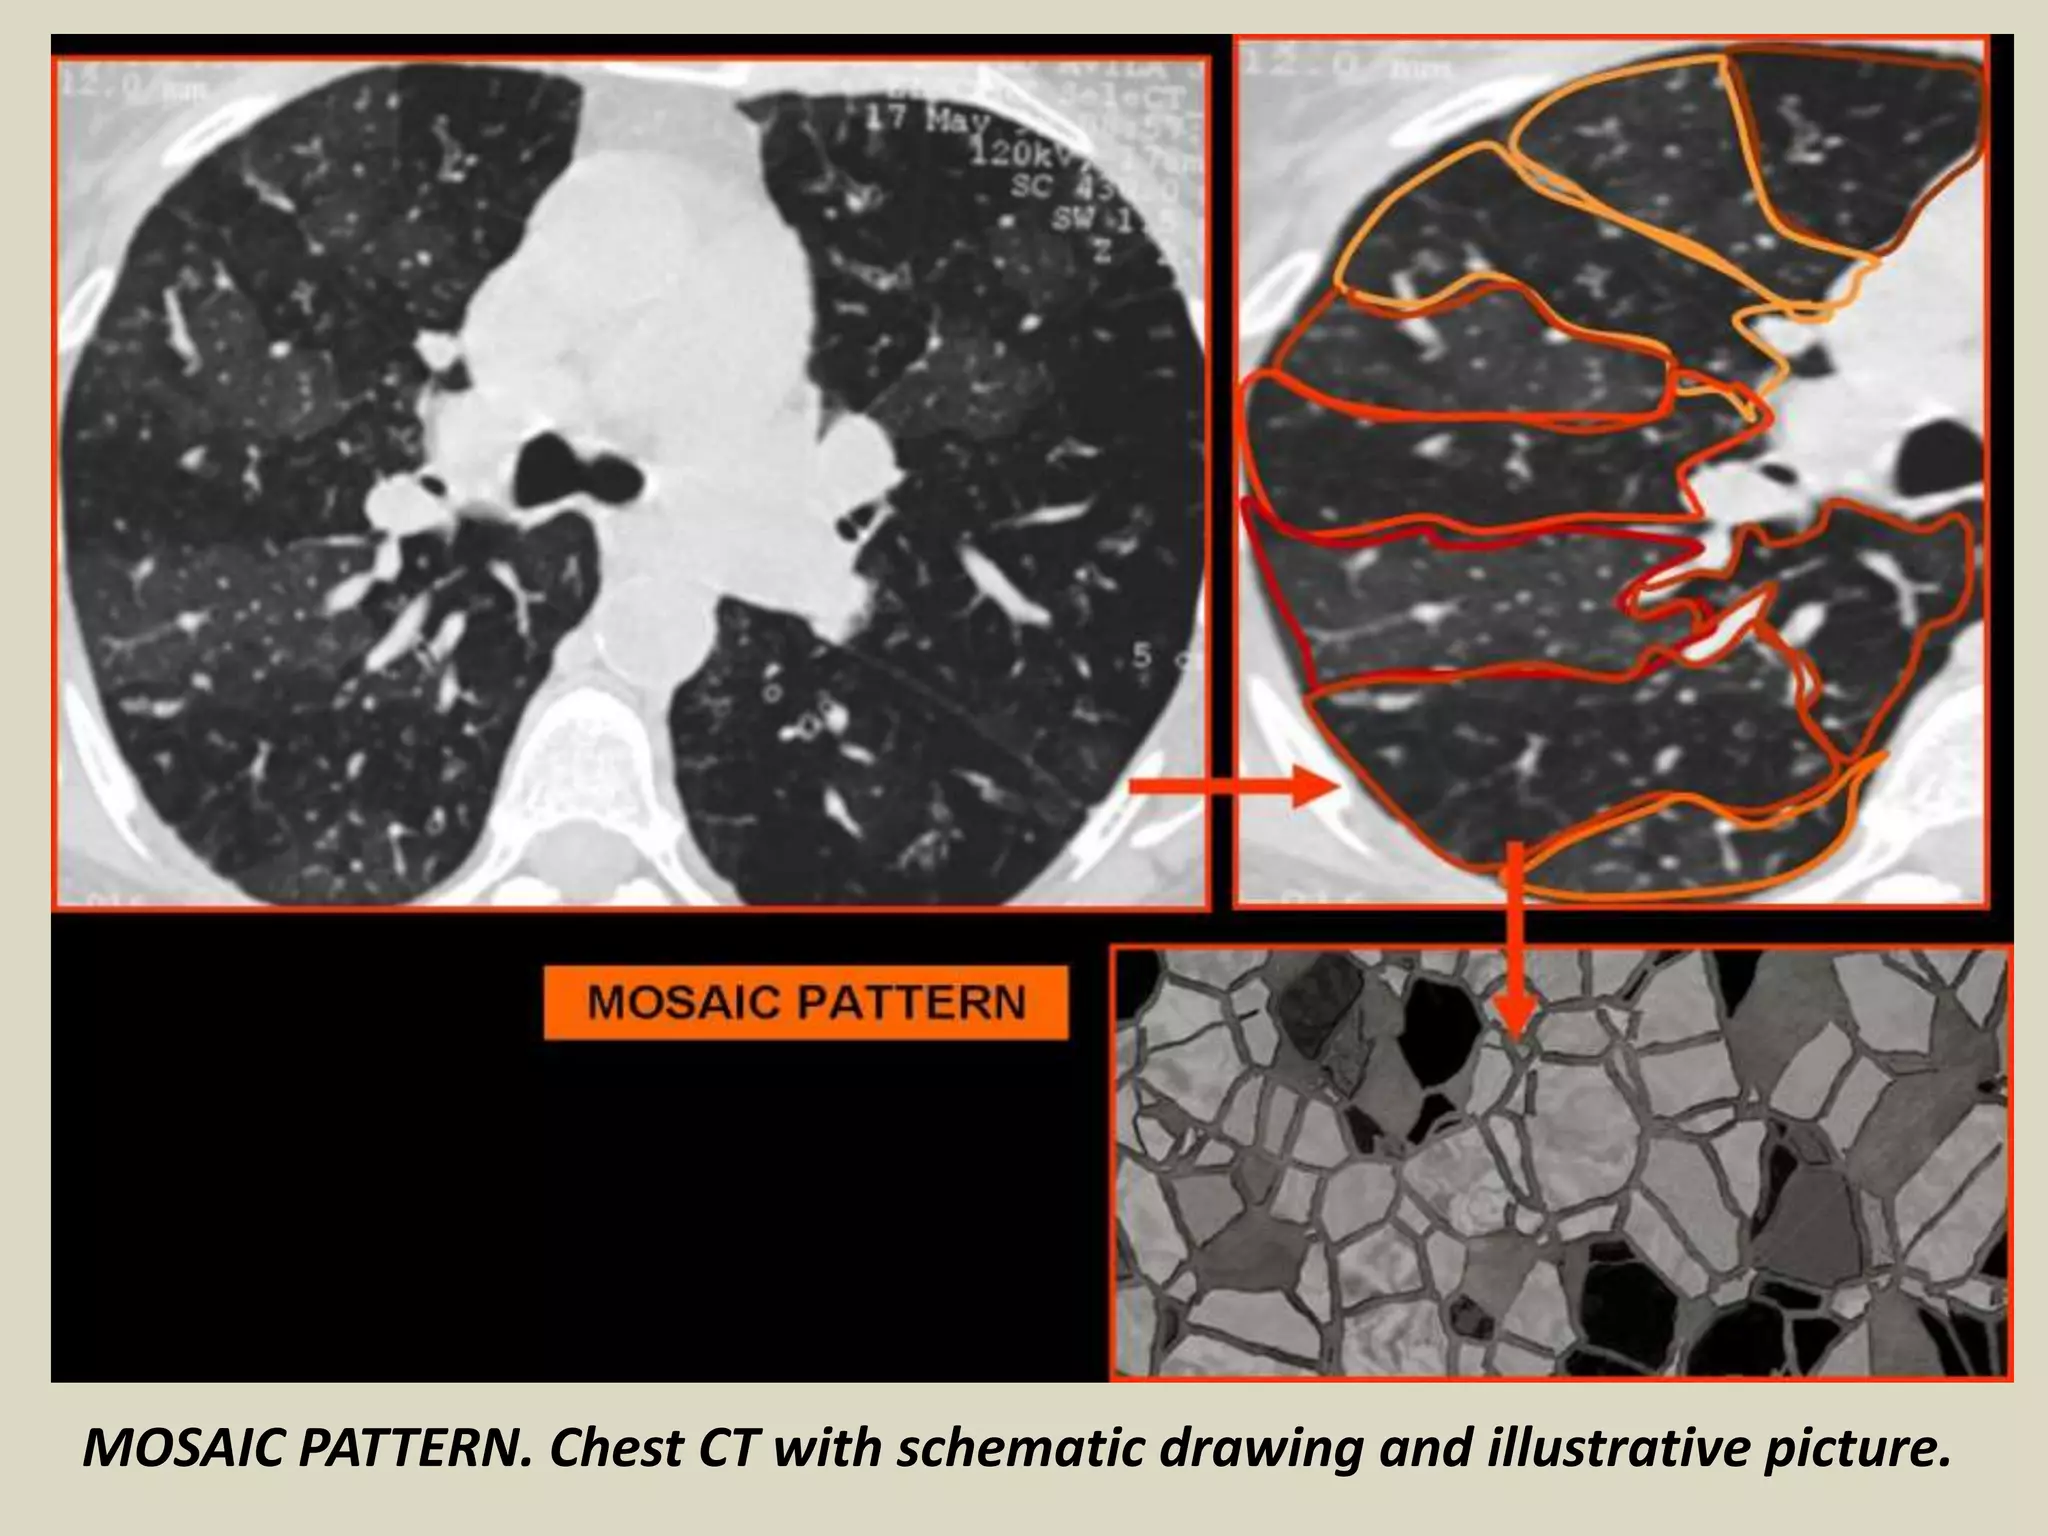

MOSAIC PATTERN

Patchy ground glass opacities, resulting in a mosaic

pattern of lung attenuation

Such a pattern can be seen in infiltrative lung disease,

airway abnormalities (e.g., asthma, bronchiolitis

obliterans), and chronic pulmonary vascular disease

(e.g., chronic thromboembolic disease)

The distinction between these three entities can be

made by observing the size of the pulmonary vessels

in the area of increased lung attenuation (increased in

both airway disease and vascular disease, but not in

infiltrative disease), and by examining air trapping on

expiratory scans (indicating airway disease)

MOSAIC PATTERN. Chest CT with schematic drawing and illustrative picture.

MOSAIC PATTERN Patchy groundglass opacities, resulting in a mosaic pattern of lung attenuation Such a pattern can be seen in infiltrative lung disease, airway abnormalities (e.g., asthma, bronchiolitis obliterans), and chronic pulmonary vascular disease (e.g., chronic thromboembolic disease) The distinction between these three entities can be made by observing the size of the pulmonary vessels in the area of increased lung attenuation (increased in both airway disease and vascular disease, but not in infiltrative disease), and by examining air trapping on expiratory scans (indicating airway disease)

MOSAIC PATTERN. ChestCT with schematic drawing and illustrative picture.